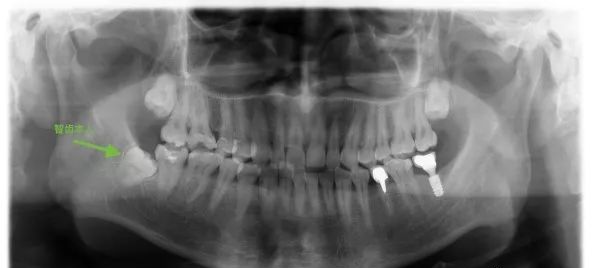

直到前几天,大白牙君在一个同学群里看到了这几张图,就突然想到了这个选题:拔智齿为什么那么贵?

大家要是比对一下自己的全景 X 片,看着那些还没来得及拔掉的智齿,有没有人会觉得自己简直「负债上亿」!

比如这种:

拔个智齿,为什么这么贵?

拔个智齿,为什么这么贵?706 / 作者:健康小天使 / 帖子ID:289504

图片来源:作者提供

这可怎么拔出来?